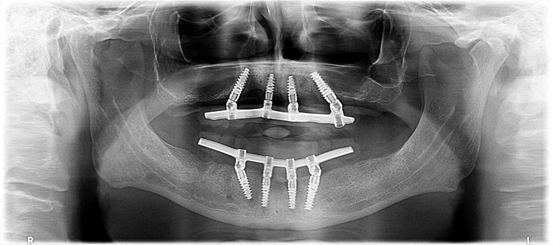

All On Four implant tekniği, tamamen dişsiz çenelere sahip olan hastalara belirli açılarla yerleştirilen dört adet implant dişin üzerine aynı gün geçici olarak hazırlanmış diş protezinin sabitlenmesiyle gerçekleşen bir prosedürdür.

All on four implant tekniğinin geliştirilme amacı alt ve üst çenelerin dişsiz arka bölgelerindeki anatomik kısıtlamalar nedeniyle implant dişin yapılmasının zor yada imkansız olduğu hastalara sabit protez dişin yapılmasına imkan tanımaktır. Bu implant tekniğinde tamamen dişsiz çenelerin ön bölgesine birbirine paralel iki adet implant arka bölgelerine doğru olan kısımlarına ise özel bir açı ile iki adet dental implant yapılır ve aynı gün hastanın kullanabileceği ve implant dişlere sabitlenen bir geçici protez yapılıp ağıza uygulanır.

Dişsiz çenelerde çekim yapıldıktan sonra azı dişleri bölgelerinde hızlıca kemik erimesi meydana gelir ve kalan kemik miktarının azalmasından dolayı arka bölgelere implant diş yapabilmenin iki metodu vardır. İlk yöntem kaybolan kemik miktarını geri kazanmak için ogmentasyon cerrahisi (kemik oluşturma) yapmaktır ve bu durumda implant dişleri yapabilmek için önce bu yapılan kemik tedavisinin başaralı olması gerekmektedir ve bekleme süresi uzamaktadır. Diğer bir yöntem ise all on four implant tekniğidir ve bu teknikte kemik erimesi nedeniyle çenelerin önemli anatomik yapılarından uzaklaşarak implant dişleri yapmak mümkündür çünkü alt çene içerisinden geçen ve merkezi bir sinir olan mandibuler sinirin üst çenede mevcut olan sinüslere müdahalede bulunmadan cerrahi prosedürü tamamlayabilmekteyiz.

All On Four implant tedavisi öncesinde detaylı ağız içi ve radyolojik muayene gereklidir. Yapılan ağız içi muayene, röntgen ölçümleri ve değerlendirmesi sonucunda hastaya uygulanacak implant çap ve uzunlukları planlanır.

Daha sonra işlem yapılacak dişsiz çene bölgesi lokal olarak uyuşturulur ve diş eti üzerinde uygun dizaynda kesi yapılarak alttaki kemik doku açığa çıkarılır. Çene kemiği üzerinde gerekli düzenlemeler protez için yapılır ve daha sonraki aşamada cerrahi şablon ile implant diş yapılacak bölgelere uygun yuvalar hazırlanır. Bu alanlara planlanan çap ve boydaki implantlar ön bölgelere birbirine paralel arka bölgelere açılı şekilde yerleştirilir.